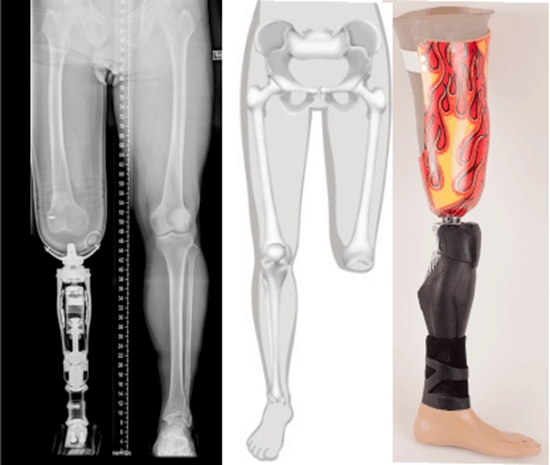

- وقتی ﻛﻪ زﺧﻢ ﻣﺤﻞ ﺟﺮاﺣﻲ ﺷﻤﺎ ﺑﻄﻮر ﻛﺎﻣﻞ ﺧﻮب ﺷﺪ ﺑﺎﻳﺪ ﺳﻌﻲ ﻛﻨﻴﺪ در ﺗﻤﺎم ﻃﻮل روز ﭘﺮوﺗﺰ ﺧﻮد را ﺑﭙﻮﺷﻴﺪ.ﺻﺒﺢ ﻛﻪ از ﺧﻮاب ﺑﺮﺧﺎﺳﺘﻴﺪ اول ﭘﺮوﺗﺰ ﺧﻮد را ﺑﭙﻮﺷﻴـﺪ و ﮔـﺮﻧـﻪ اﺳﺘﺎﻣﭗ ﺷﻤﺎ ورم ﻛﺮده و ﭘﻮﺷﻴﺪن آﻧﺮا دﺷﻮار ﻣﻴﻜﻨﺪ.

- ﺑﺎﻳﺪ از ﭘﺮوﺗﺰ ﺧﻮد ﺧﻮب ﻣﺮاﻗﺒﺖ ﻛﻨﻴﺪ. اﮔﺮ ﭘﺮوﺗـﺰ ﺷـﻤـﺎ ﻣﺸﻜﻠﻲ دارد ﺳﻌﻲ ﻧﻜﻨﻴﺪ ﺧﻮدﺗﺎن آﻧﺮا درﺳﺖ ﻛﻨـﻴـﺪ ﺑـﺎ ﺗﻜﻨﺴﻴﻦ ارﺗﻮﭘﺪى ﻛﻪ آﻧﺮا ﺑﺮاى ﺷﻤﺎ درﺳﺖ ﻛﺮده ﺗـﻤـﺎس ﺑﮕﻴﺮﻳﺪ. ﭘﺮوﺗﺰ ﺷﻤﺎ ﺣﺘﻲ اﮔﺮ ﺑﻪ ﻇﺎﻫﺮ ﺳﺎﻟﻢ ﺑﺎﺷﺪ ﺑﺎﻳﺪ ﺳﺎﻟـﻲ ﻳﻚ ﺑﺎر ﺗﻮﺳﻂ ﺗﻜﻨﺴﻴﻦ ارﺗﻮﭘﺪى ﻓﻨﻲ ﻛﻪ آﻧﺮا درﺳﺖ ﻛﺮده بازبینی ﺷﻮد.